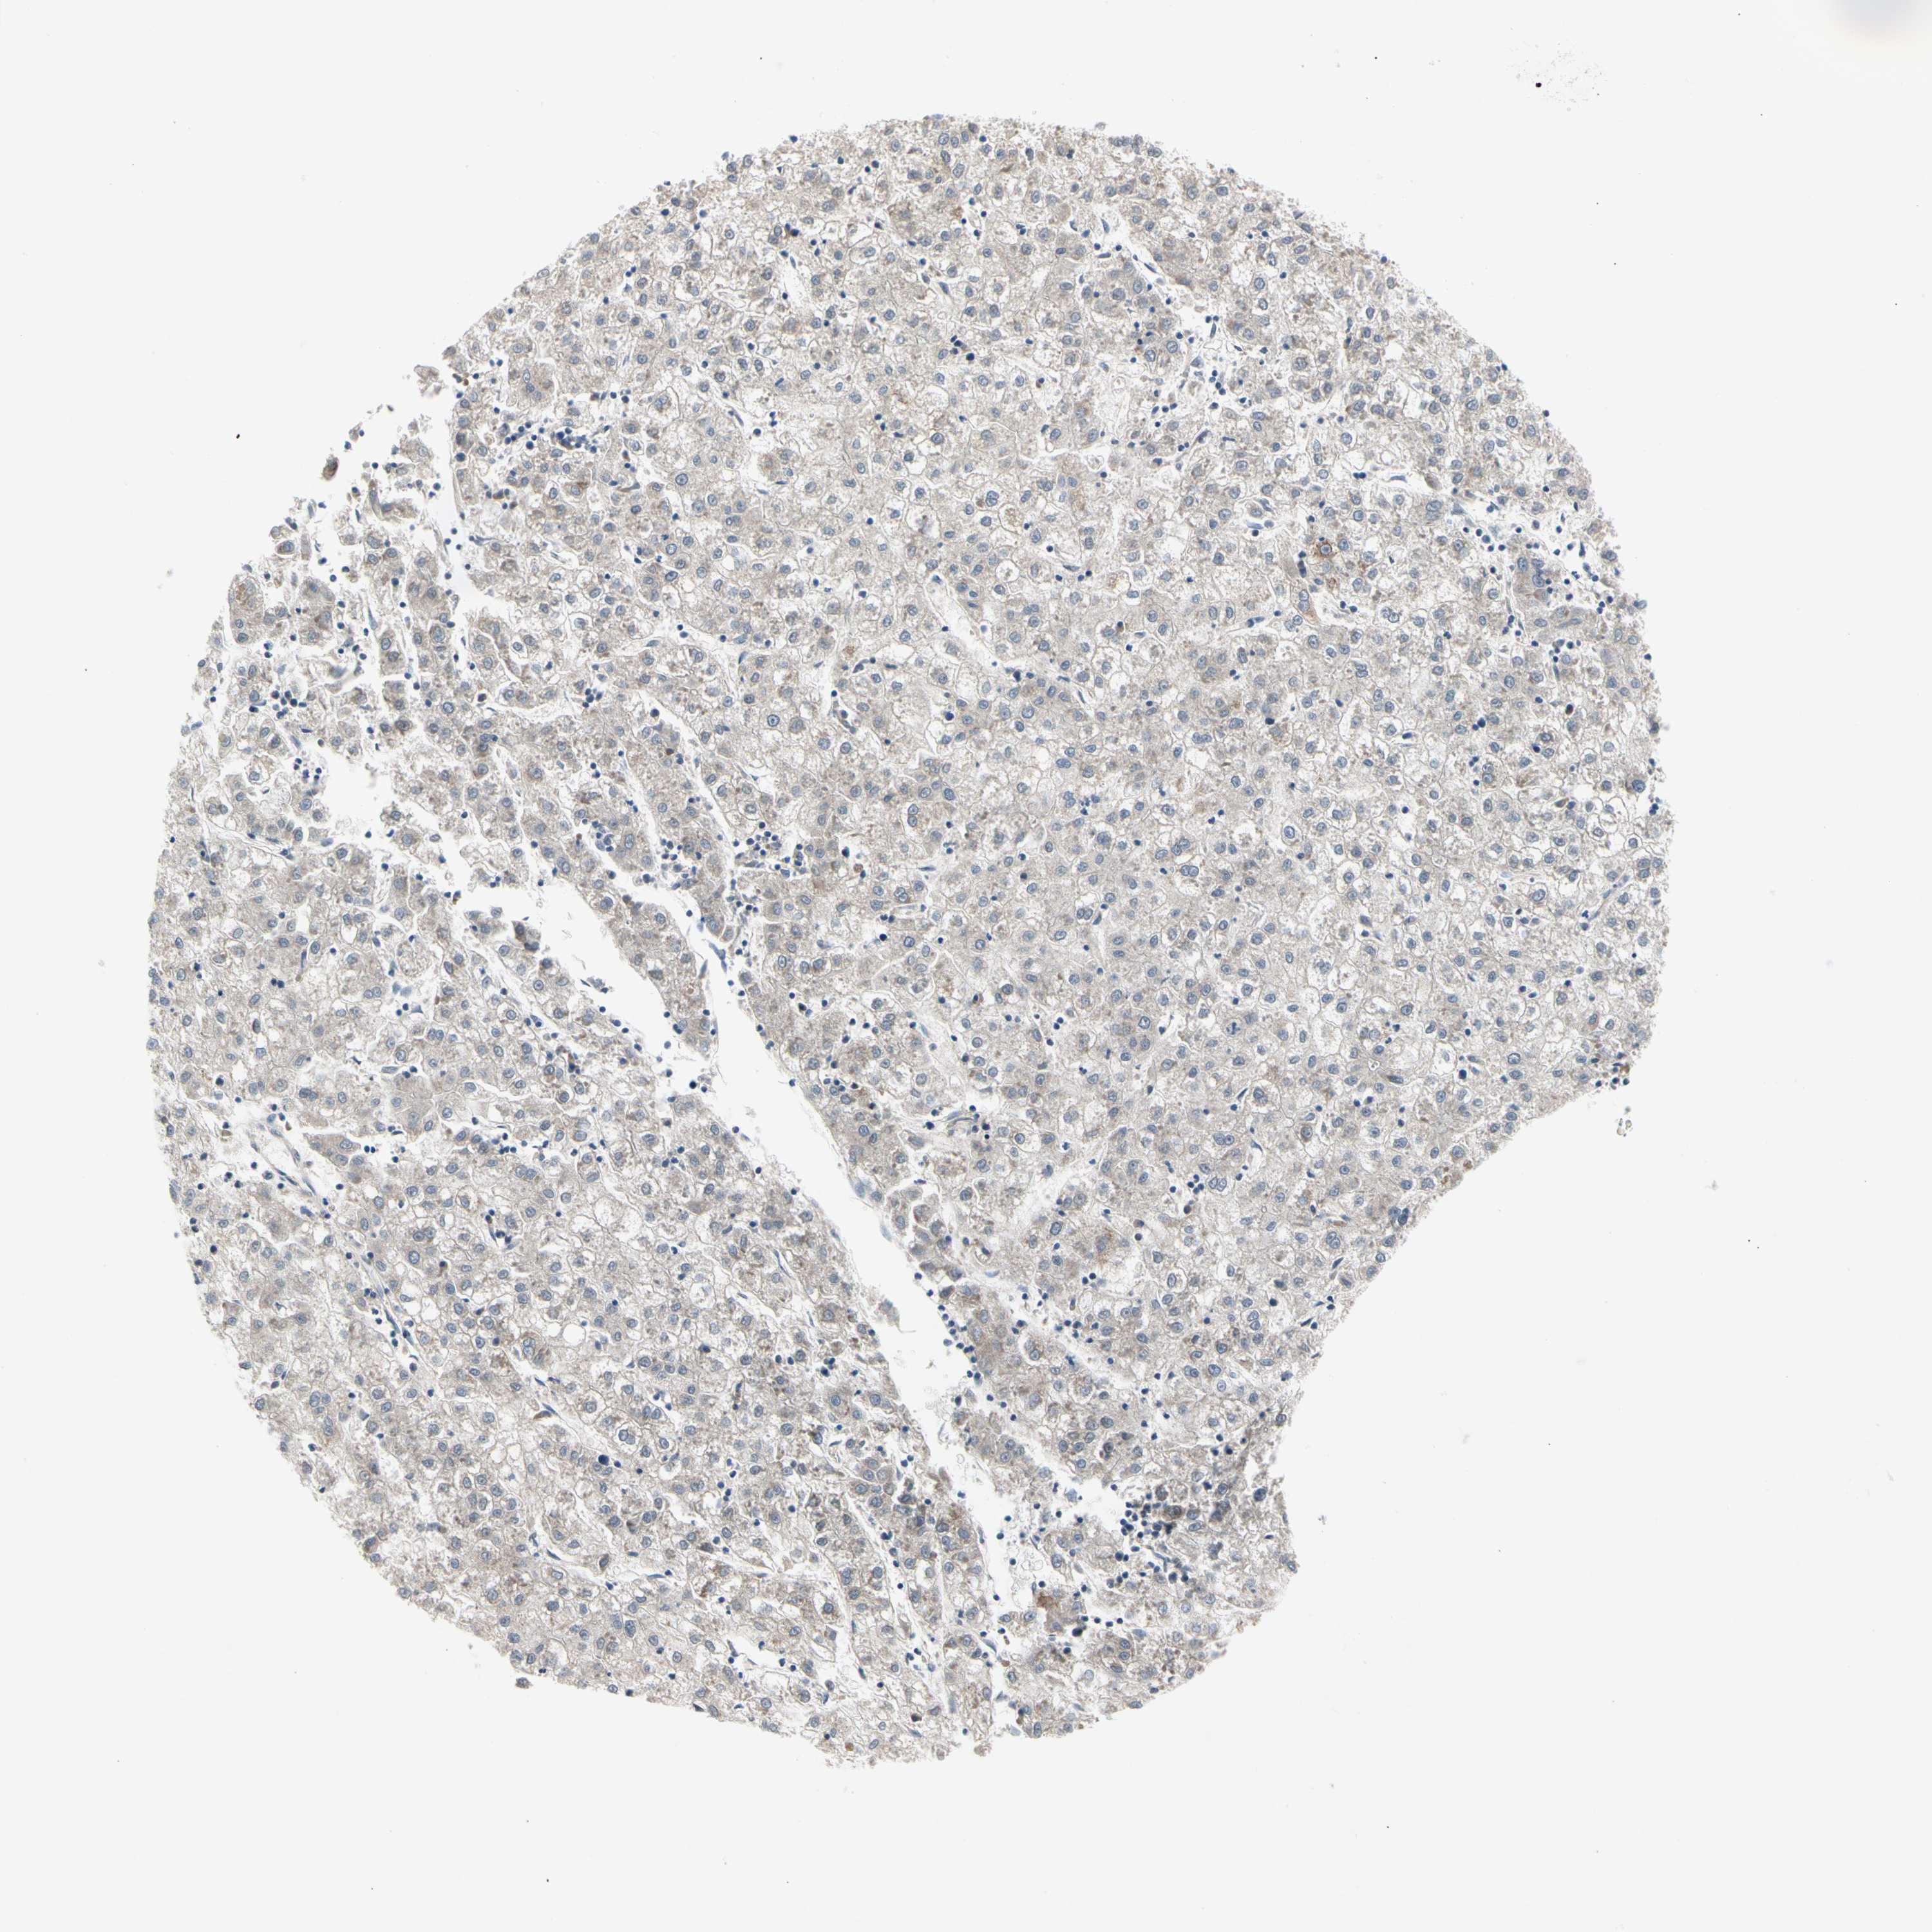

LIVER CANCER - Protein expressioni

A mouse-over function shows sample information and annotation data. Click on an image to view it in a full screen mode. Samples can be filtered based on level of antibody staining by selecting one or several of the following categories: high, medium, low and not detected. The assay and annotation is described here.

Note that samples used for immunohistochemistry by the Human Protein Atlas do not correspond to samples in the TCGA dataset.

Antibody stainingi

Antibody staining in the annotated cell types in the current human tissue is reported as not detected, low, medium, or high, based on conventional immunohistochemistry profiling in selected tissues. This score is based on the combination of the staining intensity and fraction of stained cells.

Each image is clickable and will lead to virtual microscopy that enables deeper exploration of all samples and also displays staining intensity scores, fraction scores and subcellular localization as well as patient and tissue information for each sample.

Antibody HPA007421

Antibody HPA008061

Staining

High

Medium

Low

Not detected

Intensity

Strong

Moderate

Weak

Negative

Quantity

>75%

75%-25%

<25%

None

Location

Nuclear

Cytoplasmic/membranous

Cytoplasmic/membranous,nuclear

Cholangiocarcinoma

Carcinoma, Hepatocellular, NOS